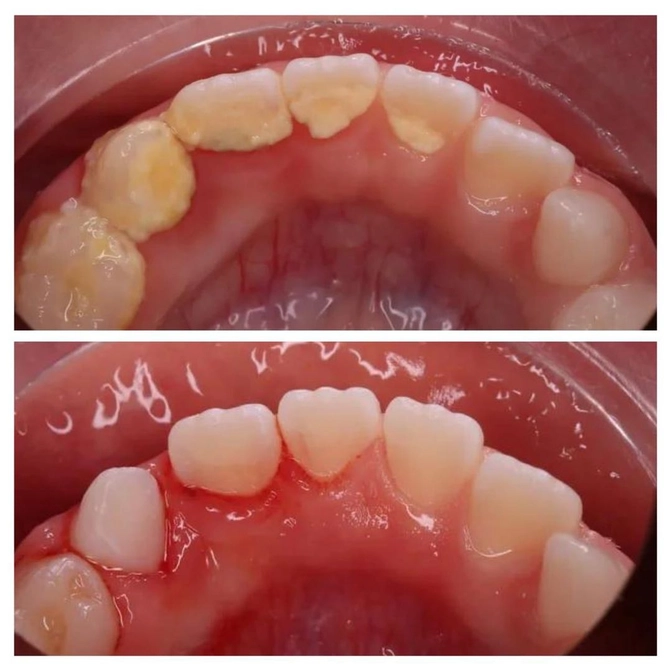

На нижних зубах с внутренней стороны образовался зубной камень.

В кабинете специальной насадкой детский стоматолог Ольга Новикова убрала с зубов пациента весь камень, все очистила и заполировала.

На фото видна небольшая кровоточивость десны.

Это гингивит — воспаление краевой части десны из-за зубного камня.